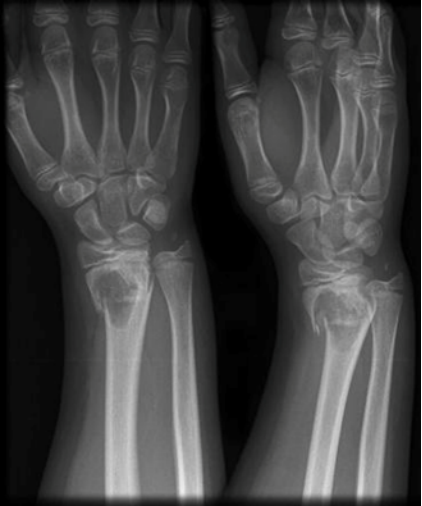

绝大多数是因为骨头上长了肿瘤,肿瘤破坏了骨的稳定和强度。就像这张照片里,肿瘤已经吃空了这个孩子手腕的骨头(桡骨),洗脸后拧毛巾,手腕就断了。